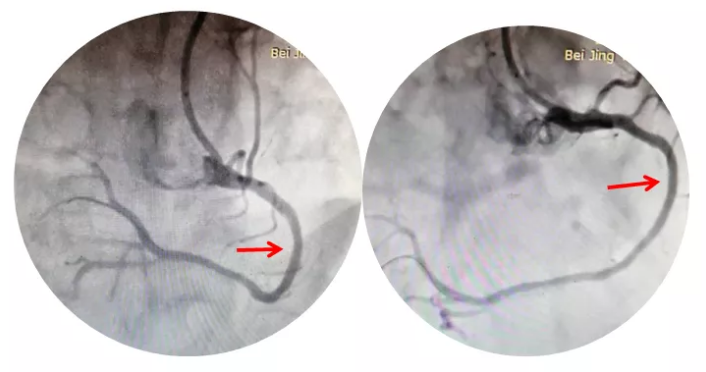

图二:患者OCT图像:纤维斑块为主,最重处管腔面积1.85mm²。

图三:冠脉支架植入后,血管狭窄问题得到改善,血流通畅。

准备就绪后,在北京阜外医院专家指导下,我科李钢主任和王志勇副主任医师上台迅速完成造影,发现患者前降支狭窄80%,对角支狭窄80%,右冠状动脉狭窄90%,征得患者同意后,在OCT指导下给予患者右冠状动脉植入支架一枚。经过一个小时的手术时间,成功完成了这台非比寻常的冠脉支架植入术。